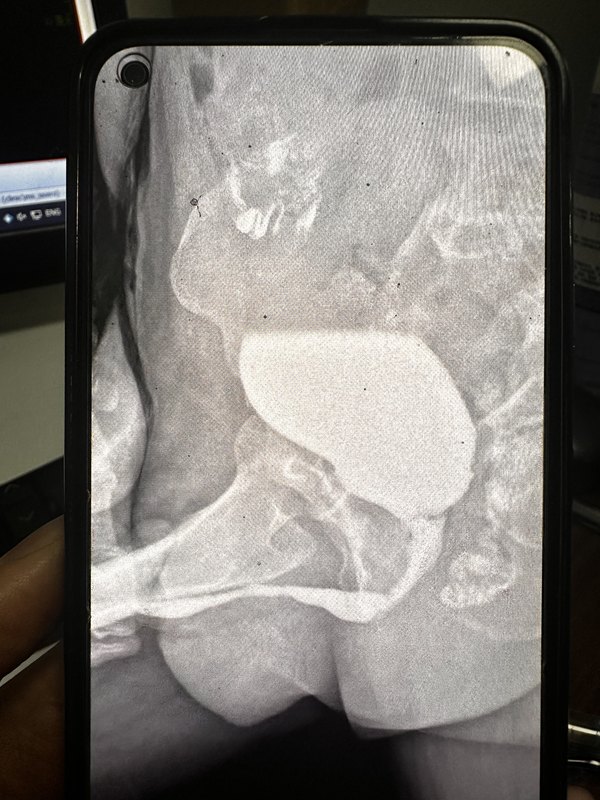

患者62歲男性,備受前列腺增生困擾,反復(fù)尿頻尿急,夜尿增多,排尿費力。今年鼓起勇氣把前列腺增生手術(shù)做了,做完手術(shù)后拔出尿管逐漸排尿不暢,一開始以為感染,后消炎效果欠佳,到后面排尿更加困難,費力,癥狀比以前沒做手術(shù)還難受,直到前些天直接拉不出尿,這才到醫(yī)院就診。結(jié)果到醫(yī)院,反復(fù)留置導(dǎo)尿管發(fā)現(xiàn)放不進去,甚至最小號的尿管也放不進去,考慮尿道狹窄,住院急診膀胱造瘺,后尿道膀胱造影,提示前尿道狹窄,長約3cm。做好檢查后,采用包皮橫行皮瓣給他做了尿道修復(fù)手術(shù),目前術(shù)后一個月,拔出尿管后患者小便通暢。在這里也提醒大家,前列腺術(shù)后復(fù)查很重要。